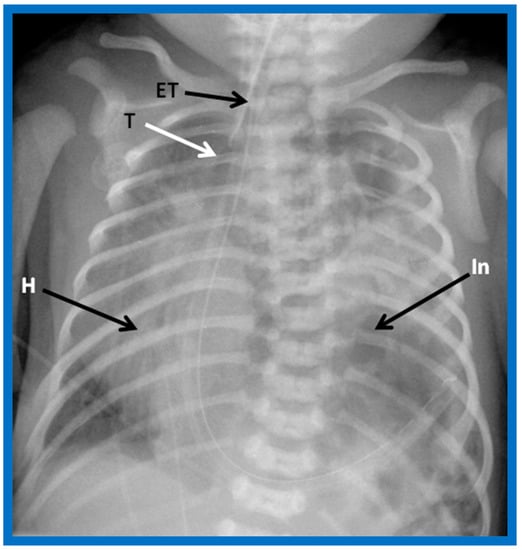

Figure 7. A chest roentgenogram of an infant demonstrating dextroposed heart (H) secondary to diaphragmatic hernia on the left side. The abdominal contents, including intestines (In) are relocated to the left side of the chest because of the diaphragmatic defect, pushing the heart into the right chest. The trachea (T) is displaced to the right. ET, endotracheal tube. Reproduced from reference [4].

3.5. Situs Solitus